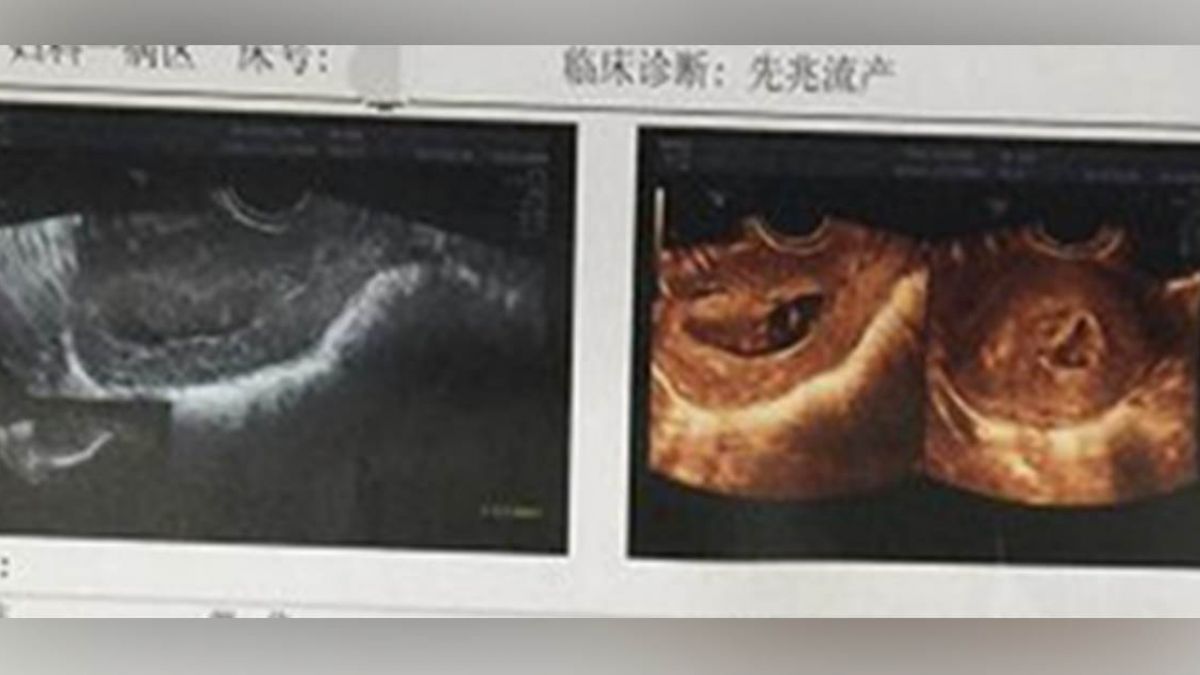

搞烏龍害命!大陸河南鄭州大學第三附屬醫院有一名護士,竟誤把孕婦禁藥當成安胎藥,傻傻地拿給31歲的李姓孕婦服用,李女不疑有他吞下,當下也沒有什麼不良反應,沒想到天照超音波檢查時,發現肚子裡懷胎好幾月的胎兒居然停止心跳,即便李女邊哭邊用手指催吐,希望把禁藥給吐出來,卻還是挽不回孩子的性命,最終流產。

「婦可靖膠囊」是專門給墮胎婦人吃的藥,有「活血化瘀」的效用。「吃錯藥」的消息傳到李女家人耳中,他們拼命地趕到醫院,李女姊姊心痛地說「見到妹妹一直在吐,也一直在哭,整個人都崩潰了。」他們看了好擔心、好緊張,醫生這時安慰說「這個藥對孕婦的影響尚不明確,不過應該也沒有關係,問題不大。」但隔天,李女做超音波檢查時,肚子裡的小寶貝居然沒了呼吸心跳,不幸宣告流產。